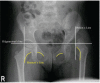

Figure 1

Pelvis X-Ray (AP view) showing left sided dysplastic hip with femur head lying in the upper outer quadrant and disrupted Shenton's line.